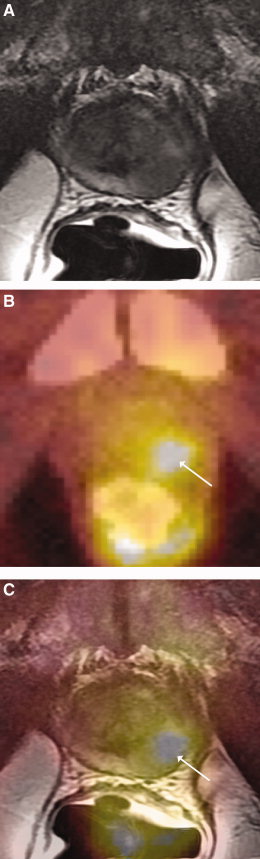

![Representative images from 3-T MRI and [18F]FDG PET/CT examinations in a 70-year-old man with PSA level of 8.0 ng/mL and Gleason score of 8 (4 + 4) prostate cancer (arrow) located in the left posterolateral prostate within the peripheral zone: (A) transverse T2-weighted image, (B) transverse fused [18F]FDG PET/CT image, (C) transverse fused [18F]FDG PET/CT image overlaid on T2-weighted MRI.](https://i0.wp.com/pharmaceuticalintelligence.com/wp-content/uploads/2013/01/fig-13-prostate.jpg?resize=260%2C859)